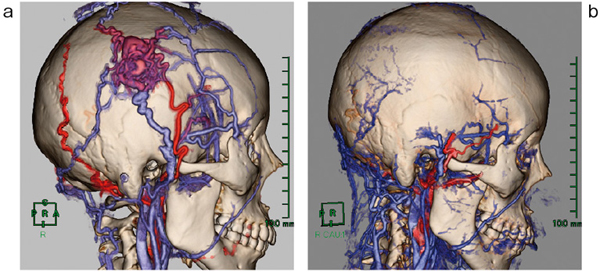

一般的に,AVMの血液循環は急速であるため,動脈優位相で流出血管の描出が予想できる。そのため,静脈優位相を撮影することによって,動脈優位相の流出血管の同定が可能であると考えられた。単純・動静脈優位相の3相をVirtualPlaceに転送し,サブトラクション機能にて動脈優位相から単純を差分して流入動脈,nidus,一部の流出静脈の三次元画像を取得することができる。また同様に,静脈優位相から単純を差分することによって,流出静脈相の画像が取得できる(図1)。そして,動脈優位相と静脈優位相の血管を色分けして表示し,マルチボリューム機能により,色の重なりの強い部分と弱い部分から動脈と静脈を判断する。そのおのおのの三次元画像から,余分な血管を削除していくことによって,最終的にnidusを取り巻く流入・流出血管を描出した(図2)。

外頸動脈には浅側頭動脈,後耳介動脈,後頭動脈が存在しており,AVMの流入・流出血管の情報が,手術時の血管の結紮時に必要不可欠である。本症例においては,右の浅側頭動脈からnidusへ流入しているのが明瞭に描出されている。また,反対側の浅側頭動脈からも細い流入血管の存在が確認できたが,その血管を追跡していくと同側の静脈にもつながっており,nidusと動静脈の判別が困難な血管においては,画像上で色調の合成として表現した(図2)。

図2 症例1:nidus周辺の流入出血管の色分け表示

術後のフォローアップとして,同症例を同様に撮影した画像を提示する。右の浅側頭動脈,静脈が結札されnidusが切除されている(図3)。また,対側から頭頂部にかけての末梢血管を描出するために,骨のマスクを膨張させ,オパシティを調整することで頭頂部の末梢動脈も確認できた(図4)。

図3 症例1:術前・術後のVR像

a:術前のVR像 b:術後のVR像(nidusの流入出血管が切除されている)